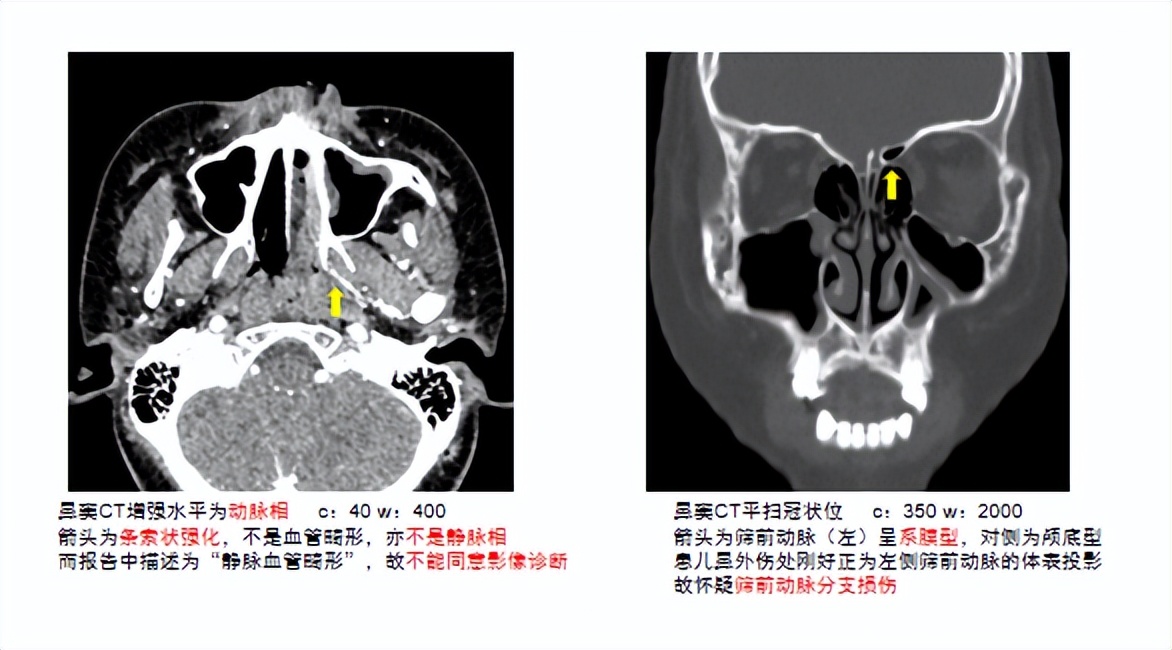

葛文彤副院长率领的耳鼻咽喉头颈外科团队再次仔细地回顾小垒的病史、充分的查体和对增强CT胶片的详细解读,最终又有了新发现——小垒的鼻出血极有可能是外伤后左侧筛前动脉分支的损伤造成的。筛前动脉来源于眼动脉,无法进行介入栓塞,否则会影响视力。